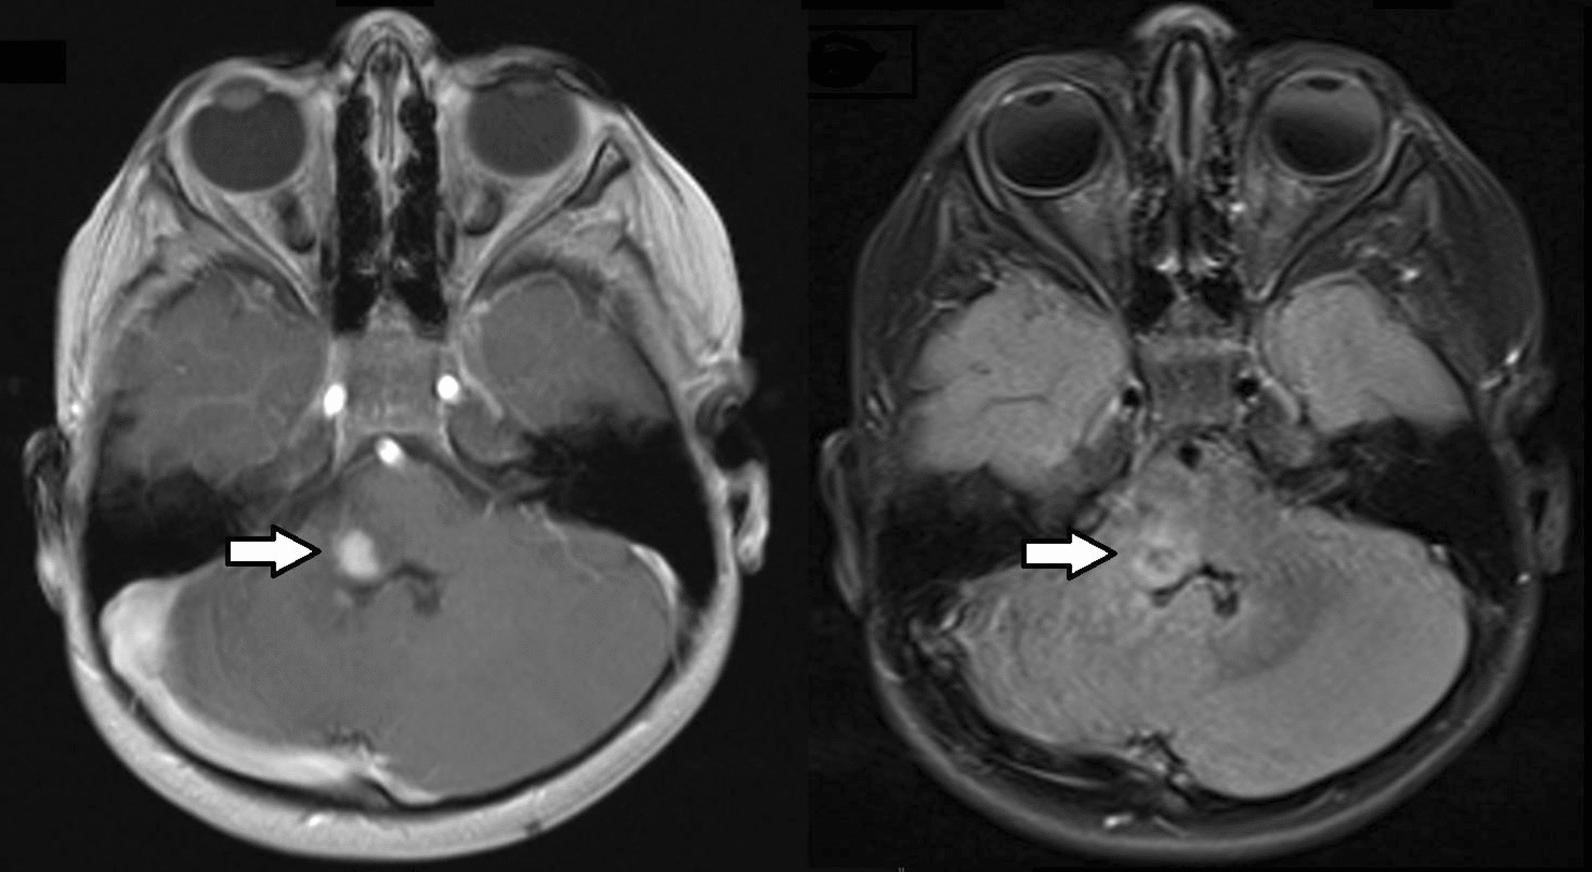

一名 4 岁女性接受了右侧髓质神经鞘瘤的次全切除术。在进行性头部倾斜的磁共振成像 (MRI) 上发现了肿瘤(图 1)。既往病史因发育迟缓和面部不对称(半面小儿)而显著。在 18 个月大时进行的先前 MRI 显示小脑发育不全,但没有肿瘤。在佳学基因进行致病基因鉴定基因解码前,采用的包括生殖系靶向基因检测包基因检测和全外显子组测序在内的综合临床基因检查结果为阴性。诊断后 8 个月的贼近一次脑部 MRI 随访显示稳定的残留病灶。

图1:T1 加权增强后(左图)和 T2/FLAIR 加权(右图)磁共振图像显示部分增强的实质内右侧髓质肿瘤(箭头)。肿瘤累及下脑桥右侧、脑桥臂和小脑腹侧